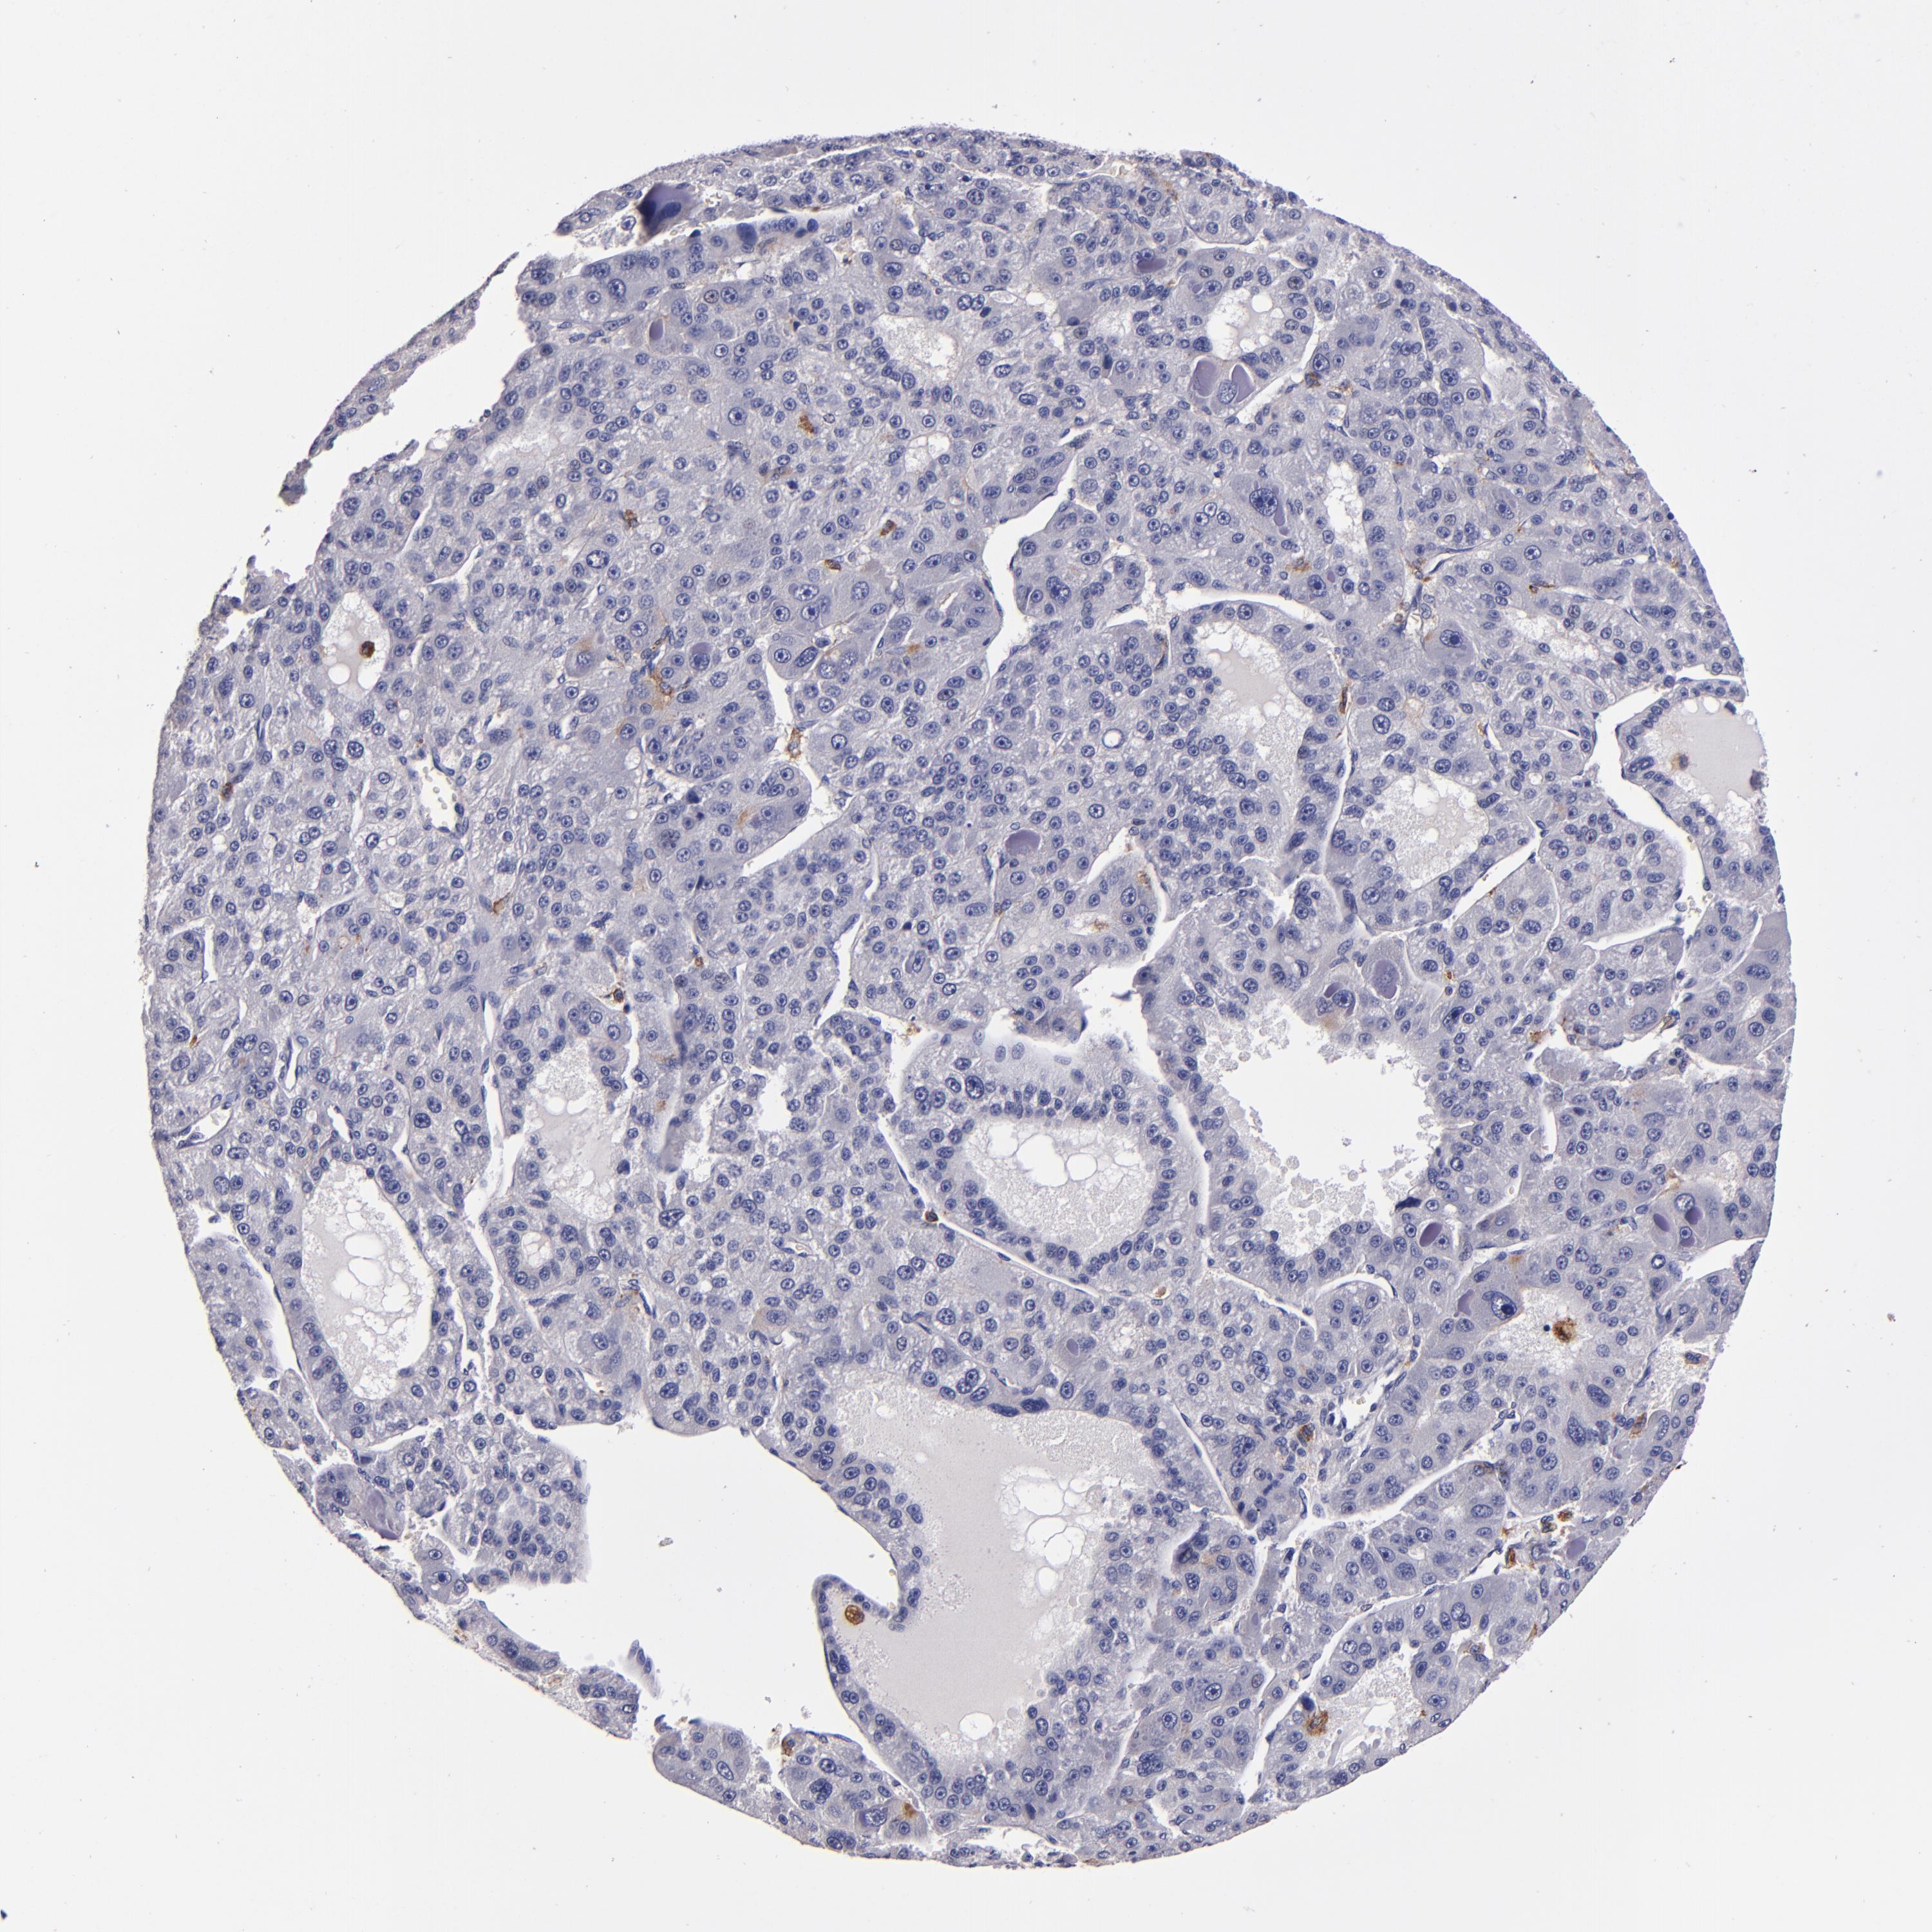

LIVER CANCER - Protein expressioni

A mouse-over function shows sample information and annotation data. Click on an image to view it in a full screen mode. Samples can be filtered based on level of antibody staining by selecting one or several of the following categories: high, medium, low and not detected. The assay and annotation is described here.

Note that samples used for immunohistochemistry by the Human Protein Atlas do not correspond to samples in the TCGA dataset.

Antibody stainingi

Antibody staining in the annotated cell types in the current human tissue is reported as not detected, low, medium, or high, based on conventional immunohistochemistry profiling in selected tissues. This score is based on the combination of the staining intensity and fraction of stained cells.

Each image is clickable and will lead to virtual microscopy that enables deeper exploration of all samples and also displays staining intensity scores, fraction scores and subcellular localization as well as patient and tissue information for each sample.

Antibody HPA054437

Antibody HPA058511

Antibody CAB002776

Antibody CAB015122

Carcinoma, Hepatocellular, NOS

Cholangiocarcinoma